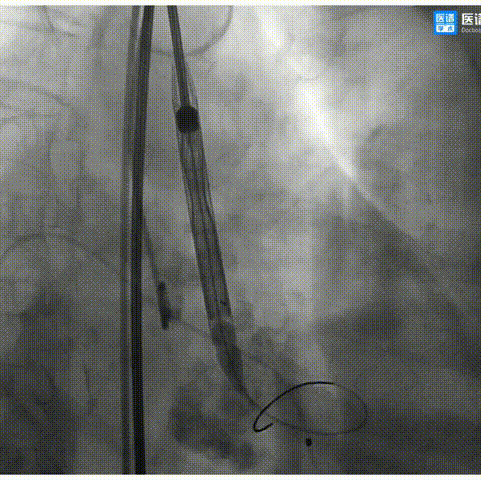

4.180次/分快速起搏下以18mm TaurusAtlas球囊进行预扩张,扩张时无明显腰征;